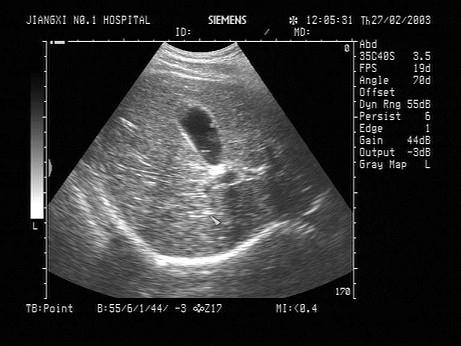

问题 女,32岁,偶感右上腹不适多年。声像图如图所示,最可能的诊断为?(?)

选项 A.胆囊结石 B.胆囊蛔虫 C.胆囊胆固醇结晶 D.胆囊息肉 E.胆囊腺瘤

答案 D